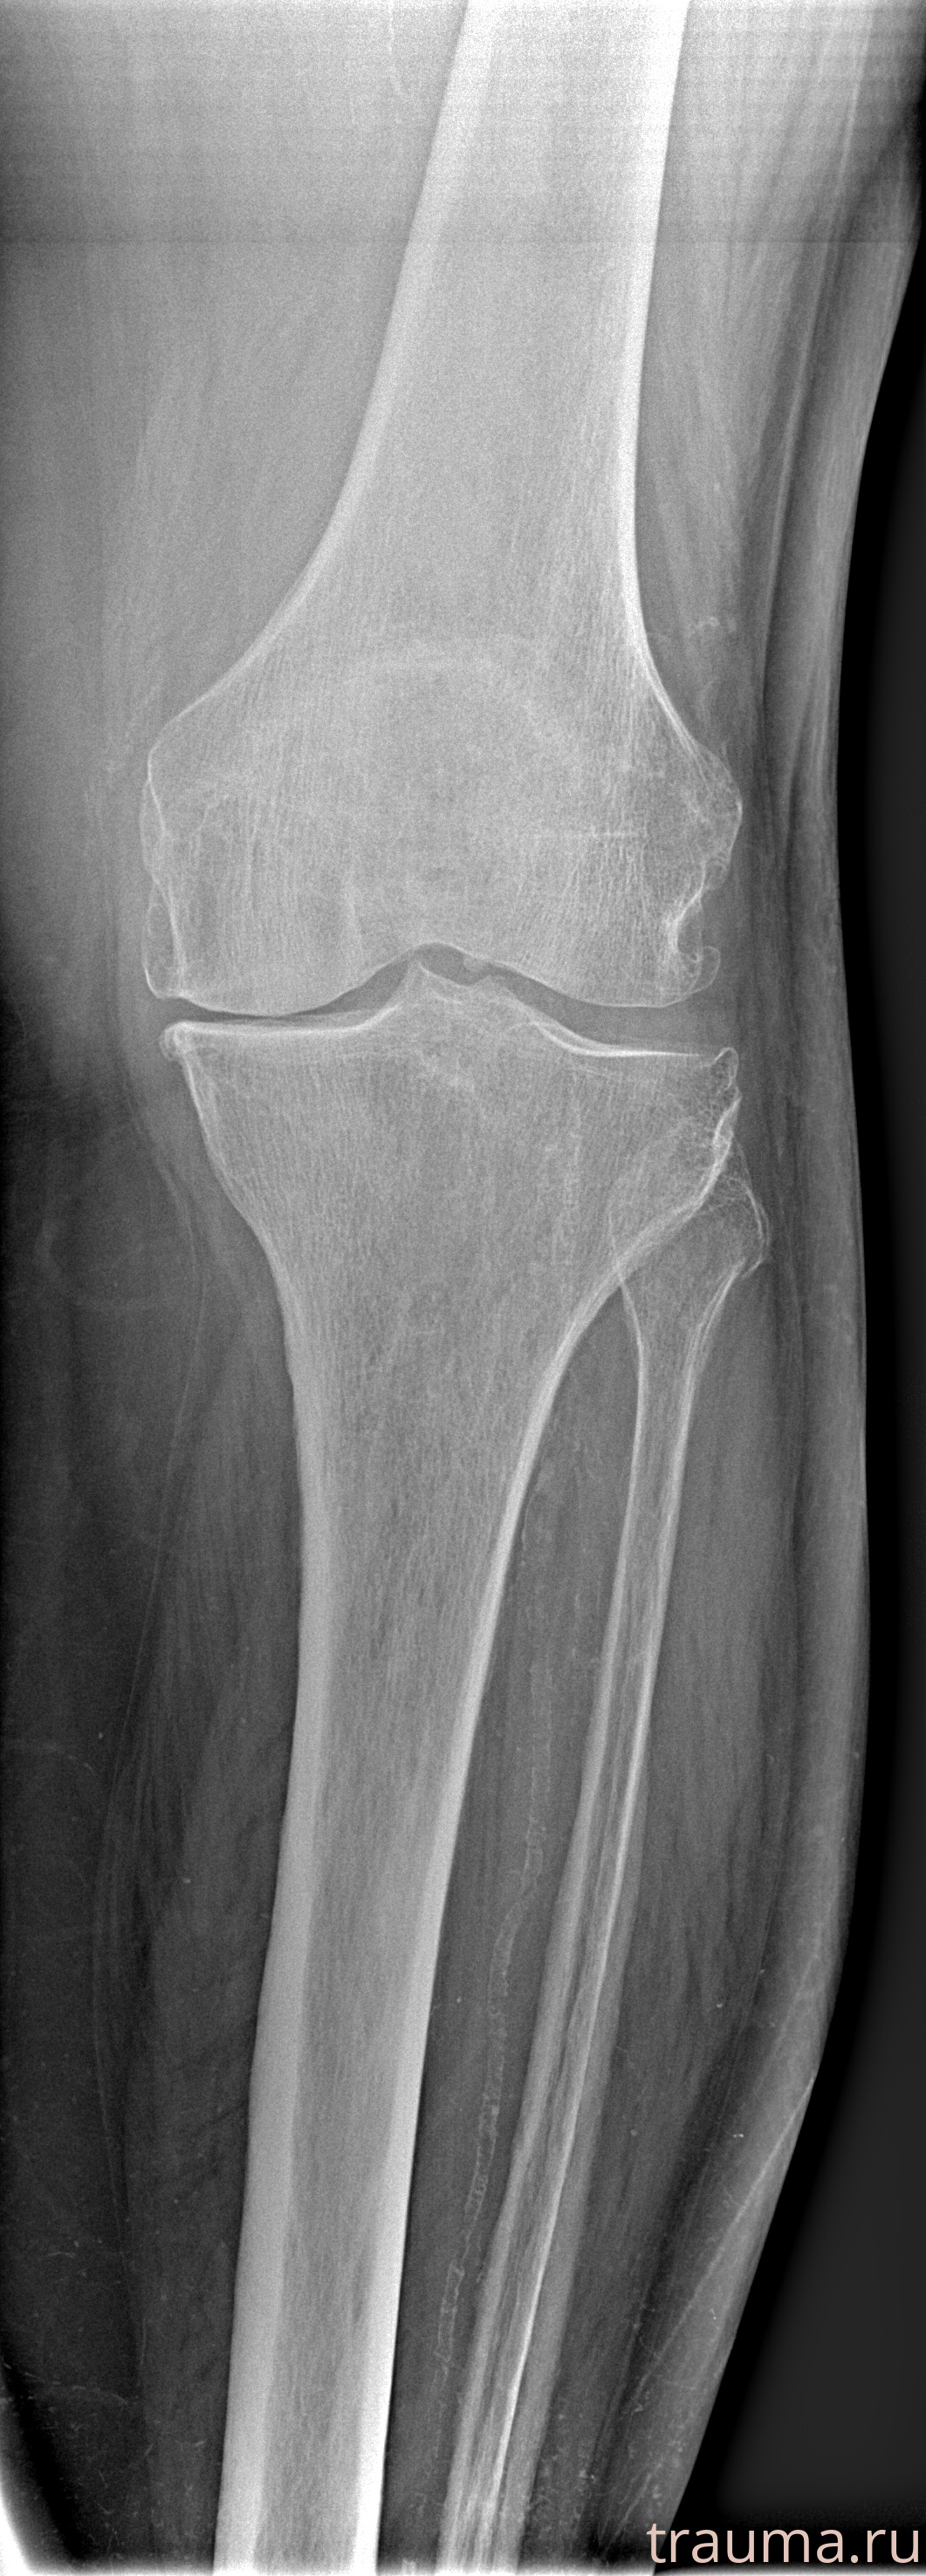

Рентгенограммы

Рентген на дому: по вашему адресу приезжает врач-рентгенолог, травматолог-ортопед с мобильным рентгеновским аппаратом, проводит диагностику травмы или заболевания, делает необходимые рентгенограммы, дает рекомендации по дальнейшему лечению. Получить качественные снимки в домашних условиях возможно благодаря уникальной методике, разработанной МосРентген Центром для института  Склифосовского